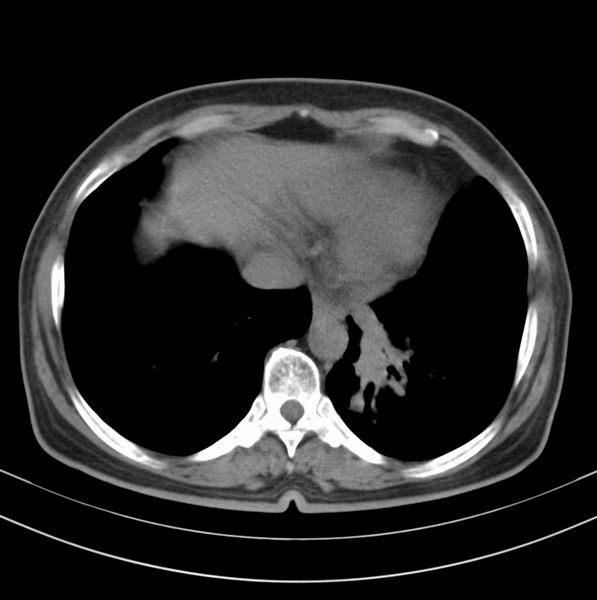

标题: CT20053:胸部增强请会诊。

女、63

咳嗽、胸痛四个月

包绕左下肺基底段的不规则的软组织肿块,段支气管腔变形、狭窄及阻塞性炎症,病变区不规则强化,又是老年女性支持楼上看法。

考虑左肺下叶中央型肺癌伴阻塞性肺炎、支气管黏液嵌塞。

典型病例:左下肺基底段中央型肺癌,相应支气管狭窄并阻塞性炎症